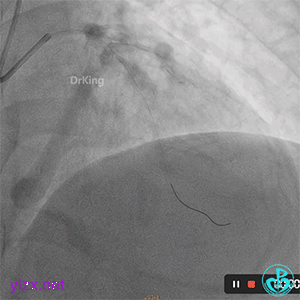

06 8天后复查冠脉造影

RCA粗大近中段瘤样扩张明显,中段血栓影消失,左室后支显影,后降支近段可见造影剂滞留, TIMI血流3-级。